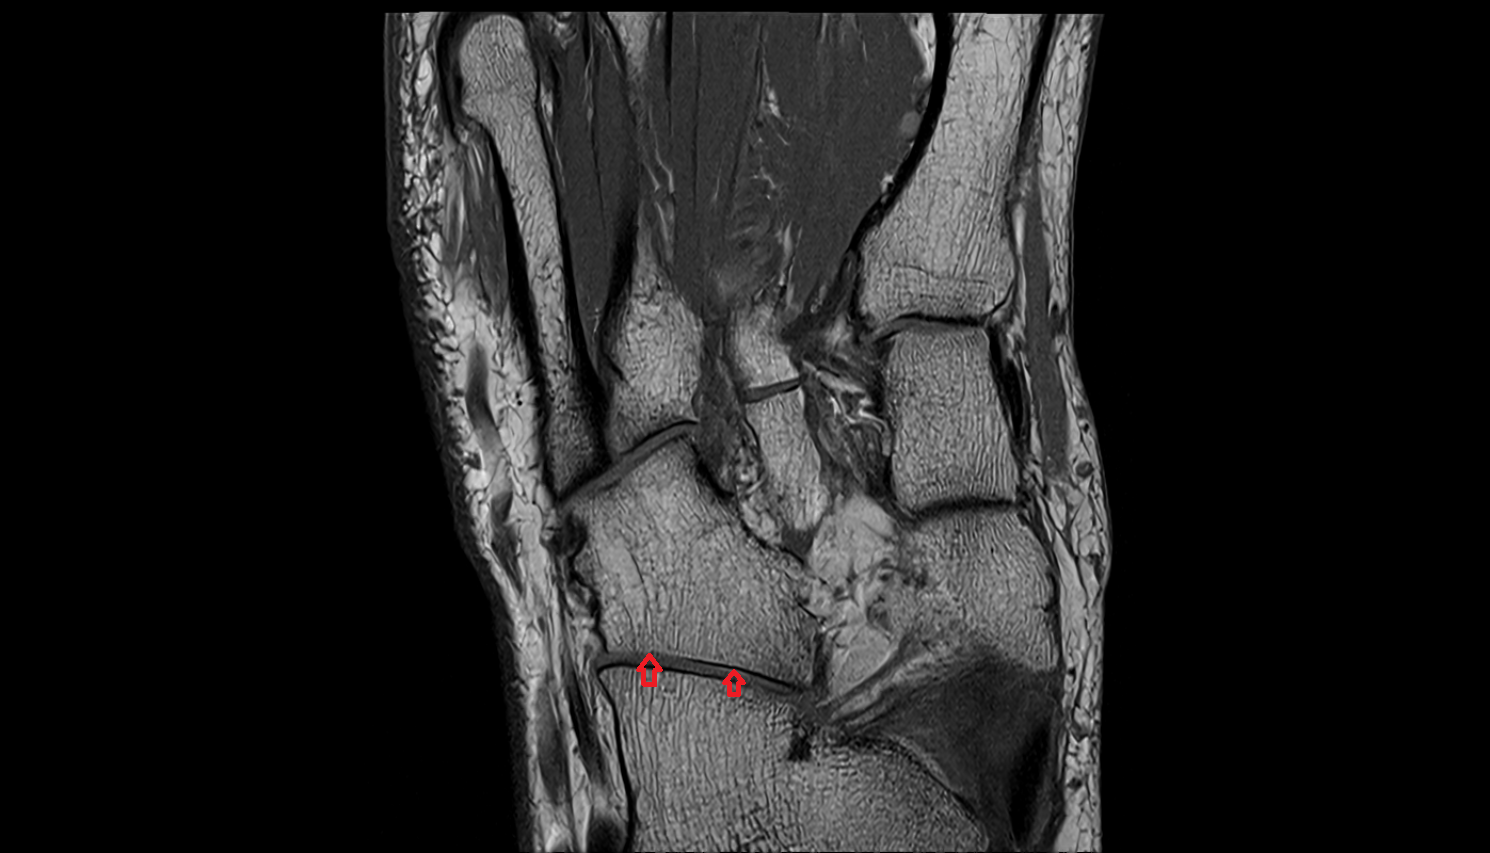

- Calcaneus

- Sustentaculum tali

- Tuberosity of navicular bone

- Cuboid

- Talocalcaneal joint

- Talocalcaneonavicular joint

- Calcaneocuboid joint

- Lateral cuneiform bone

- Medial cuneiform bone

- Intermediate cuneiform bone

- Talocalcaneal interosseous ligament

- Calcaneonavicular ligament (Bifurcate ligament)

- Calcaneocuboid ligament (Bifurcate ligament)

- Bifurcate ligament

- Spring ligament complex

- Superomedial calcaneonavicular ligament